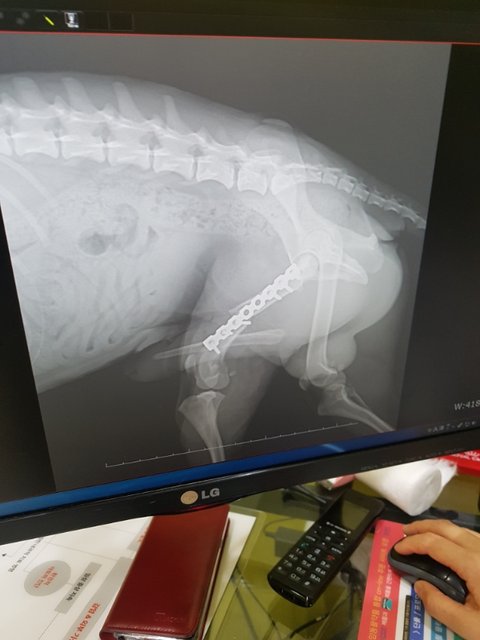

뒷다리골절 수술했습니다

우리 노아가 씩씩하게 수술을 받고 깨어났습니다

심장사상충 때문에 마취에서 못 깨어날까봐 얼마나 두려운 시간을 보냈는지 모르겠습니다

이제 한고비 넘겼습니다

회복 잘해서 사상충치료도 잘 받을수있도록 케어 잘 하겠습니다